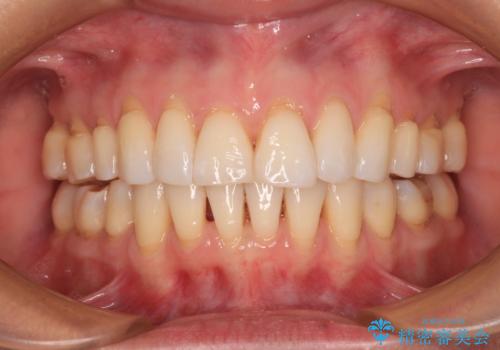

突き上げによる隙間を予防する為に、深い咬み合わせを改善するような治療計画としました。咬み合わせを改善させることはできましたが、隙間は後戻りしやすいので、通常の下顎前歯のみではなく、上顎前歯2本もワイヤーで保定を行いました。

高校生ということで、非常に短期間で治療を終えることができました。